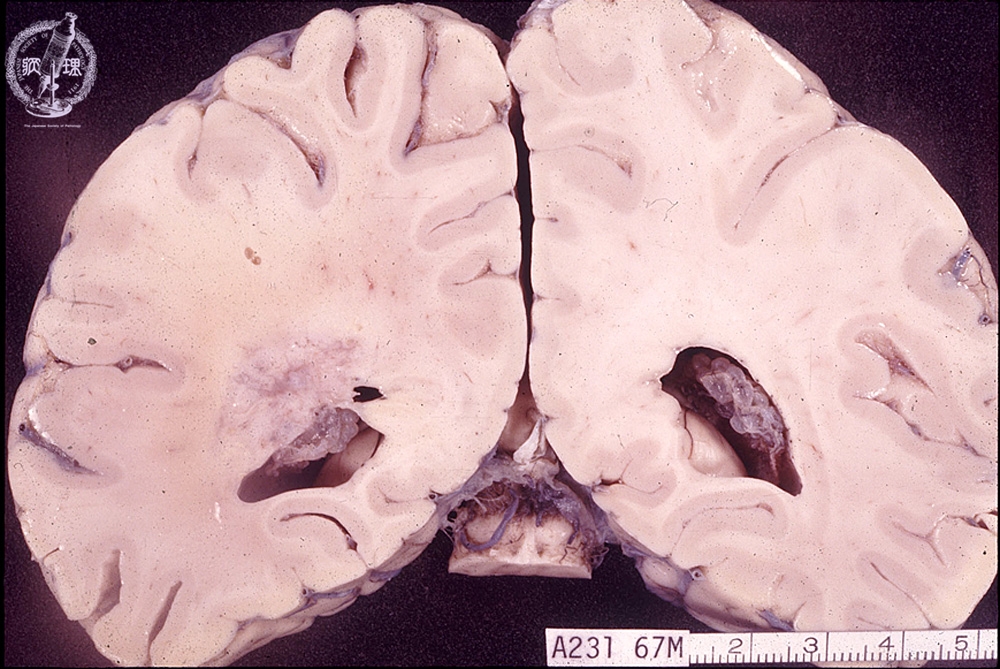

- ★(8)Glioma(Astrocytoma)

Macroscopic findings: Relatively indistinct tumor mass was detected in the lateral lobe around the left lateral ventricle (red circle).